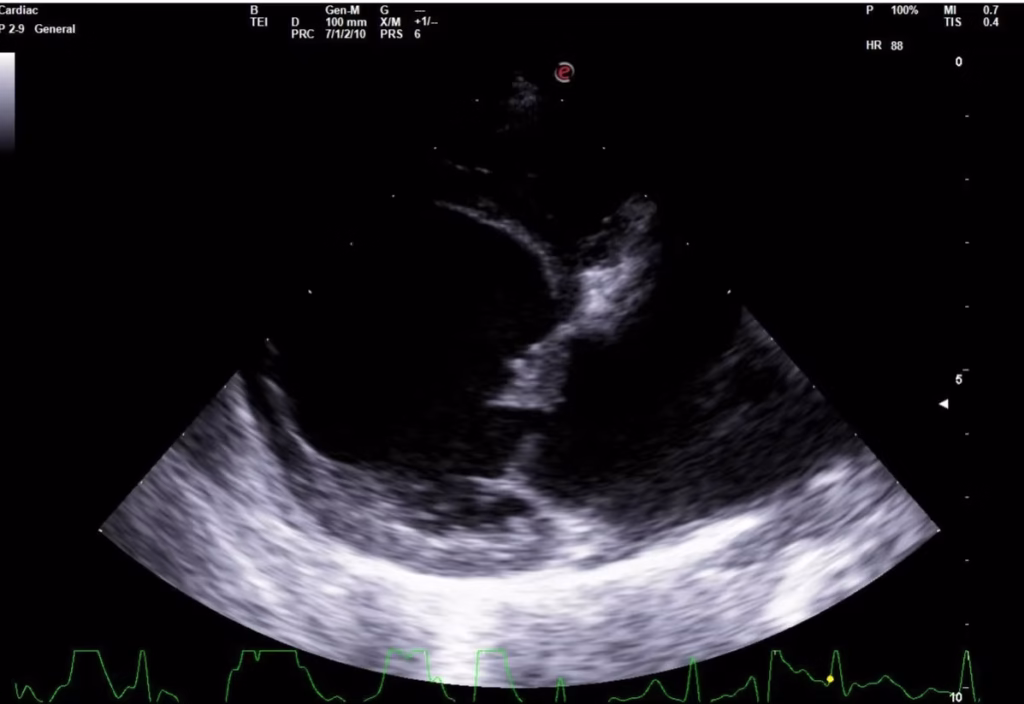

KAJ ZAJEMA KARDIOLOŠKI PREGLED?

Kardiolog bo najprej klinično pregledal celega psa, nato bo več časa namenil avskultaciji prsnega koša. Za postavljanje točne diagnoze bo potreben še UZ srca in RTG prsnega koša. Vzela se bo tudi kri, da se vidi delovanje notranjih organov, saj so pri srčnem popuščanju prizadeti organi celega telesa. Včasih je potrebno tudi te zdraviti.